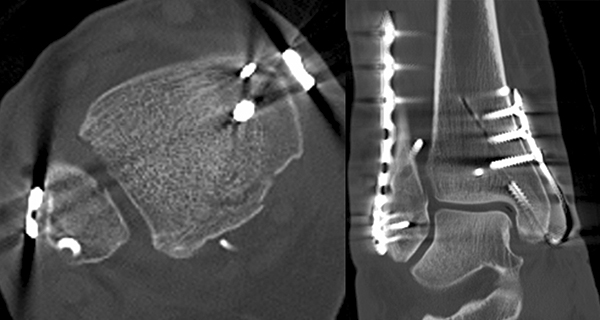

Liegt eine Fraktur des oberen Sprunggelenks vor, ist sowohl zur Entscheidung für ein konservatives oder operatives Vorgehen, als auch zur Operationsplanung, ein ausreichendes Verständnis der Fraktur und ihrer Morphologie notwendig. Insbesondere bei komplexen Verletzungen ist dafür die konventionelle Röntgenaufnahme in vielen Fällen nicht ausreichend. So konnten z.B. Black et al. zeigen, dass die operative Strategie zur Versorgung von OSG-Frakturen in 24% basierend auf einer zusätzlichen CT-Bildgebung relevant geändert wurden 7. Dies betraf die Lagerung, die Wahl des Zuganges und die Art der osteosynthetischen Versorgung. Besonders häufig änderte sich das Vorgehen bei Verletzungen des medialen (21%) und des posterioren Malleolus (15%). Darüber hinaus führten dislozierte (dislozierte Frakturen 31% vs. nicht-dislozierte Frakturen 20%) oder komplexe Frakturen (Trimalleolar-Frakturen 29% vs. Unimalleolar-Frakturen 10%) besonders häufig zu relevanten Änderungen des operativen Vorgehens. Die Computertomographie ist daher, insbesondere bei Bi- und Trimalleolar-Frakturen, essentiell für das Verständnis der Fraktur und somit für die Planung und Durchführung der Operation. In Abbildung 4 und 5 sind exemplarisch ein Röntgen- und ein CT Befund gegenübergestellt.

Liegt eine Syndesmosen-Insuffizienz vor (Abbildung 18), so erfolgt nach der Osteosynthese aller Frakturen im ersten Schritt die Reposition der Fibula in die Incisura fibularis der Tibia mittels Repositionszange. Danach sollte geprüft werden, ob die Dorsalextension im OSG noch uneingeschränkt möglich ist. Falls vorhanden, ist es hilfreich die korrekte Reposition mittels intraoperativen CT zu kontrollieren. Die Durchführung eines intraoperativen 3D Scans konnte nach zufriedenstellenden Ergebnissen in der konventionellen 2D Bildgebung bereits intraoperativ in 20-40% ein korrekturbedürftiges Ergebnis zeigen 3132. Anschließend erfolgt das Einbringen einer Stellschraube oder eines Tight Ropes (Abbildung 19). Dabei sollte darauf geachtet werden, dass die Bohrung knapp proximal des distalen Tibio-Fibular-Gelenkes angelegt wird. Die Bohrung sollte in 30° von posterior nach anterior und parallel zur Gelenklinie des OSG gerichtet sein. Beim Einbringen der Schraube ist darauf zu achten, die Fibula nicht an die Tibia zu komprimieren. Postoperativ empfehlen wir die Durchführung einer CT-Untersuchung des verletzten und des unverletzten Sprunggelenkes. Nur so ist aus unserer Sicht die Reposition der Fibula sicher zu beurteilen.